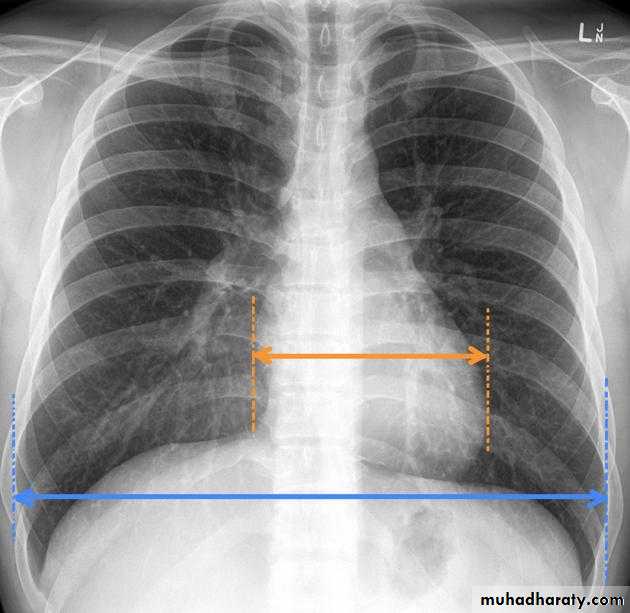

• chest radiography (cardiomegaly is suggestive of hypertensive heart disease);

Measurement of cardiothoracic ratio ( CTR)